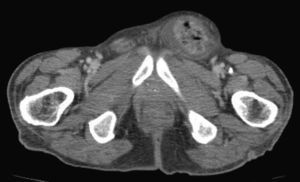

Tras la valoración por cirugía se decide pedir una TC abdominal que es informada como: «Múltiples quistes simples distribuidos en ambos lóbulos hepáticos. Marco cólico en su totalidad ocupado por heces, hernia inguinal izquierda que contiene segmento corto del sigma. Calcificación de aorta infrarrenal y ambas arterias ilíacas, alteración de la trabeculación en acetábulo y pala ilíaca del lado izquierdo» (figs. 1 y 2).

Tras las pruebas complementarias se llegó al diagnóstico definitivo de hernia inguinal incarcerada, con lo que se procedió a efectuar el tratamiento quirúrgico definitivo con carácter de urgencia. Tras la cirugía el paciente evolucionó favorablemente y le fue dada el alta con control ambulatorio. Durante el seguimiento desde la consulta de atención primaria el paciente tuvo buena evolución clínica.